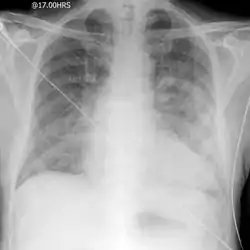

![]() صورة شعاعية لاستسقاء الرئة الحاد. صورة شعاعية لاستسقاء الرئة الحاد. | |

التشخيص يتأكيد بالأشعة السينية للرئتين، التي تظهر زيادة السوائل في الجدران السنخية (الحويصلات). خطوط كيرلى باء ، زيادة ملء الأوعية الدموية، الانصباب الجنبي، تسريب الفص العلوي (زيادة تدفق الدم إلى الأجزاء العليا من الرئة) قد تكون مؤشرا على وذمة رئوية قلبية، في حين سنخية غير منتظمه متجانسة مع برونكوجرام الهواء هي أكثر دلالة على وذمة غير قلبيه[2]